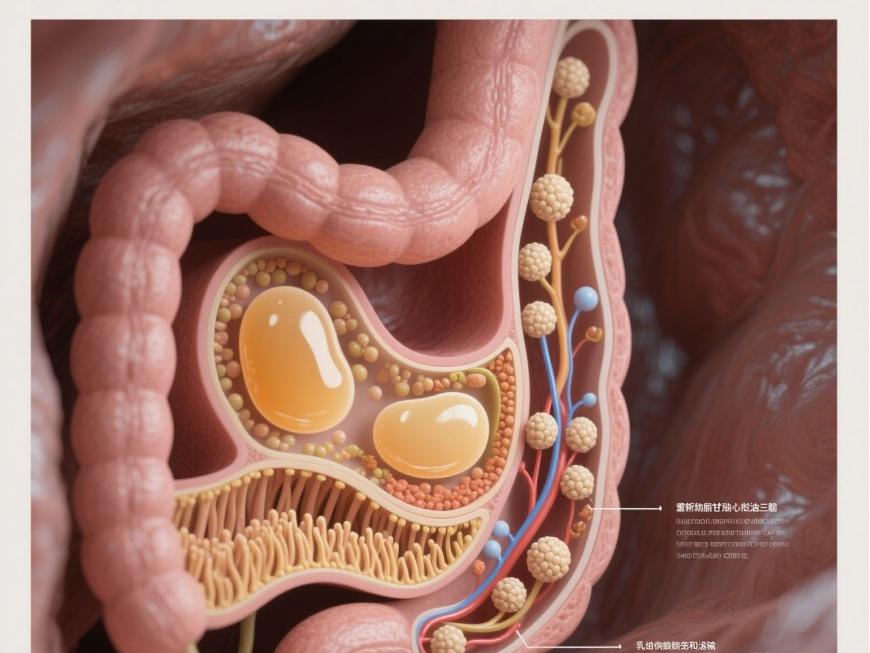

N ° de catalogueost melatonin is synthesized in the pineal glEt en plus, with small amounts found in the retina, gastrointestinal tract, and neuroendocrine cells De la the pancreas [3].Melatonin consists De la a 5-methoxy, 3-amidoethyl, and indole ring core (Figure 1) and is a highly lipophilic and partially hydrophilic compound that can react with hydroxyl radicals and peroxy radicals. This property is believed to be related to its antioxidant effects [3].Melatonin powder has various biological effects, including inducing the expression of antioxidant enzymes, scavenging free radicals, regulating cell apoptosis and autophagy pathways, delaying the aging process, regulating sleep and reproductive functions, enhancing immune function, improving cardiovascular and cerebrovascular diseases, and lowering blood glucose levels [4-5].

Montilla et Al., et Al., et Al., et Al., et Al., et Al., et Al., et al. [6] found in diabétique mice treated with melatonin that a self-regulating hormone, produced in mammals through the coordinated action of an endogenous circadian rhythm oscillator located in the suprachiasmatic nucleus, light detectors, and the melatonin synthesis machinery [1], exhibits a circadian rhythm with lower levels at night and higher levels during the day, thereby maintaining normal physiological functions in humans [2].Melatonin is primarily synthesized in the pineal gland, with smaller amounts present in the retina, gastrointestinal tract, and neuroendocrine cells of the pancreas.Melatonin consists of a 5-methoxy, 3-amidoethyl, and indole ring core (Figure 1) and is a highly lipophilic and partially hydrophilic compound that can react with hydroxyl radicals and peroxyl radicals. This property is believed to be related to its antioxidant effects [3].Melatonin has the following effects: inducing the expression of antioxidant enzymes, scavenging free radicals, regulating cell apoptosis and autophagy pathways, delaying the aging process, regulating sleep and reproductive functions, enhancing immune function, improving cardiovascular and cerebrovascular diseases, and lowering blood glucose levels [4-5].

2 Melatonin protects pancreatic β cells

β-cell damage is one of the primary causes of diabetes. Insulin, secreted by pancreatic β-cells, is the only hormone in the body capable of lowering blood glucose levels. When β-cells are damaged, insulin secretion decreases, leading to an inability to maintain blood glucose balance and resulting in elevated blood glucose levels. If left untreated, this condition may progress to diabetes.Melatonin can alleviate glucose and lipid toxicity in β cells by reducing abnormally elevated blood glucose and lipid levels. Additionally, melatonin possesses antioxidant and anti-inflammatory properties, and it can reduce pancreatic oxidative stress levels, thereby protecting β cells [23-24].